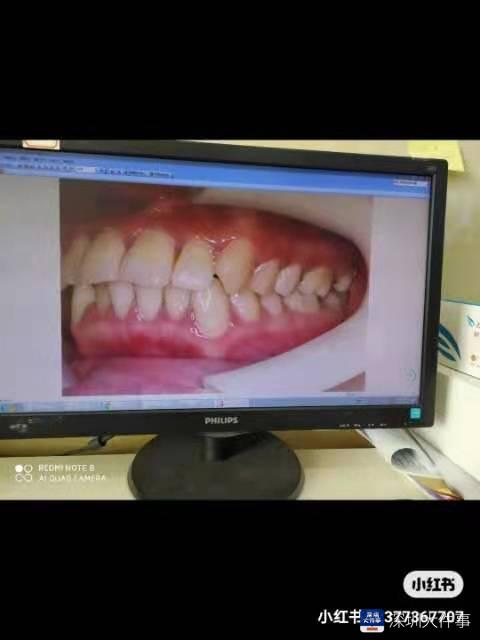

矫正前

矫正后

近日,有深圳市民向南都记者报料称,2019年开始在深圳福华医疗美容医院(下称“福华医院”)开始牙齿矫正,但是两年后的今天,牙齿不仅没有矫正好,反而牙龈几乎全部萎缩,不少牙齿松动,牙缝也越来越大。

上述市民李莉(化名)质疑,福华医院在给她拔牙矫正前未走牙龈炎治疗这一常规流程,以及矫牙过程中医生加力不当等都可能是“罪魁祸首”。

然而治疗7个月以后,牙缝也越来越大。有点惊慌的她去其他医院寻求帮助,有医生根据她在福华医院拍的牙片告诉她,她矫正牙齿前有牙龈炎,而且比较严重, 矫正前应该先治疗牙龈炎,而不是直接拔牙治疗。

除了两颗智齿,其他牙齿的牙龈全部萎缩了。李莉说:“就上下各一颗智齿没有萎缩,因为当时医生说治疗后期可能要拔掉,所以没上矫正器。其他上了矫正器的牙齿都不太结实,一取下矫正器就晃动,都快要掉了。”